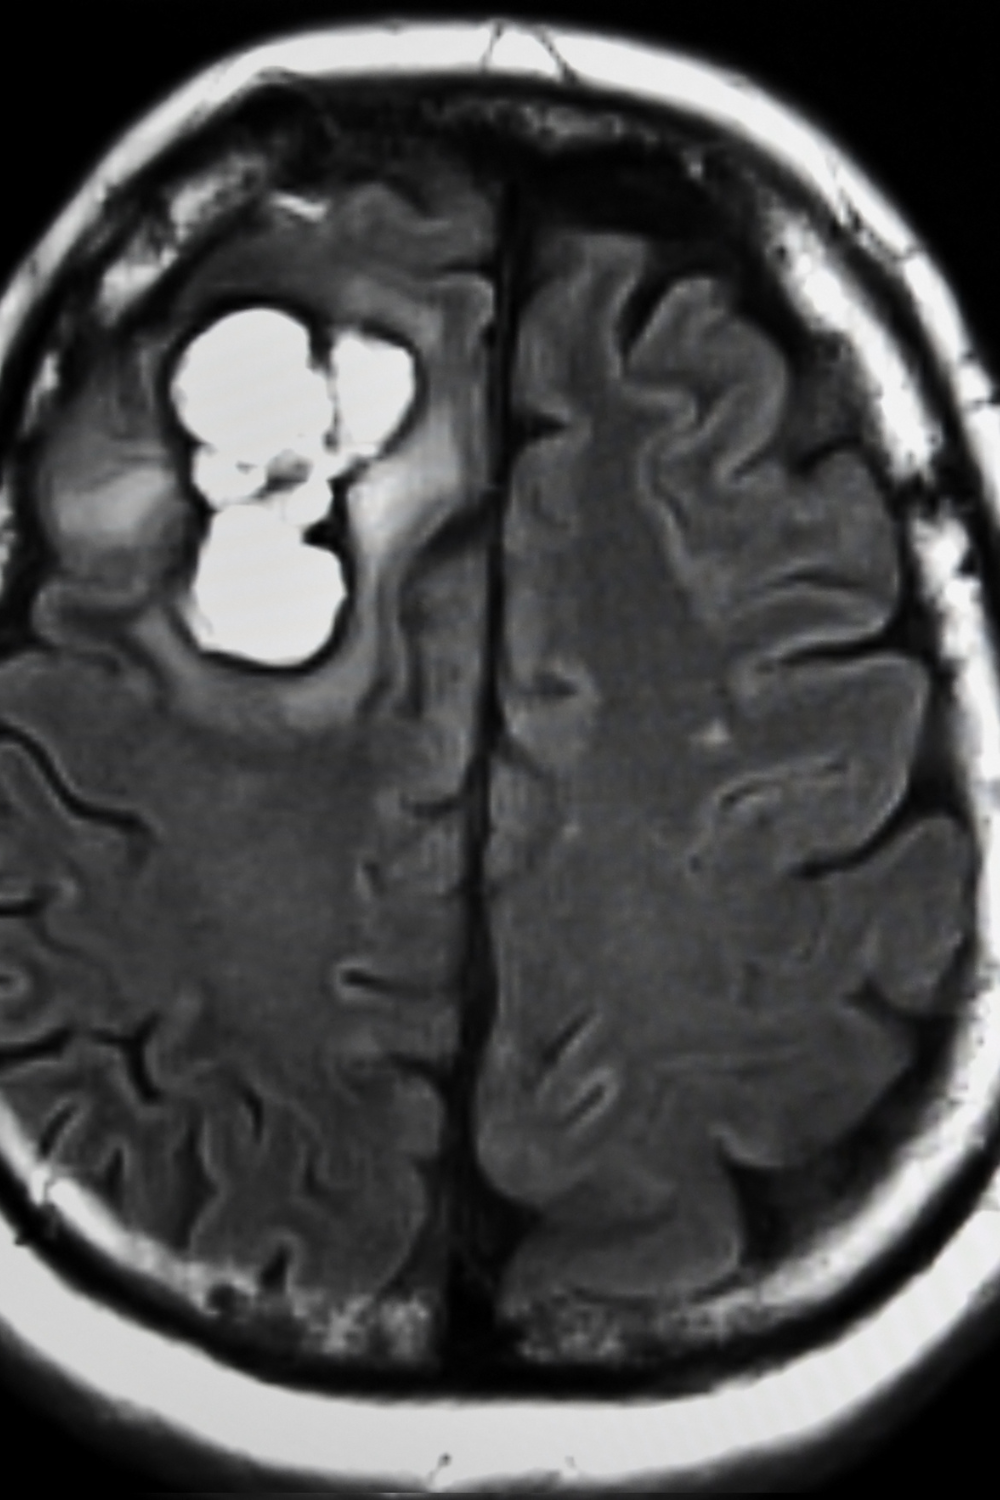

Los tumores de cerebro se caracterizan por el crecimiento de células anormales en el tejido cerebral. Los tumores pueden ser benignos (sin células de cáncer) o malignos (con células cancerígenas que crecen muy rápido). Algunos tumores se denominan primarios, o sea, que comienzan en el cerebro, otros son metastásicos, quiere decir que comenzaron en alguna otra parte del cuerpo y tienen la capacidad de invadir al cerebro.

Los tumores en el cerebro se pueden agrupar dependiendo del tipo de células que se ven afectadas (como meningiomas, gliomas, ependimomas, etc.) o por el lugar en el que se encuentran dentro del cerebro. Casi la mitad de los tumores en el cerebro no son cancerosos (son benignos), crecen lentamente y responden bien al tratamiento.

Los tumores se diagnostican por medio de un examen neurológico y pruebas de imágenes como son: tomografía computarizada, resonancia magnética, etc.